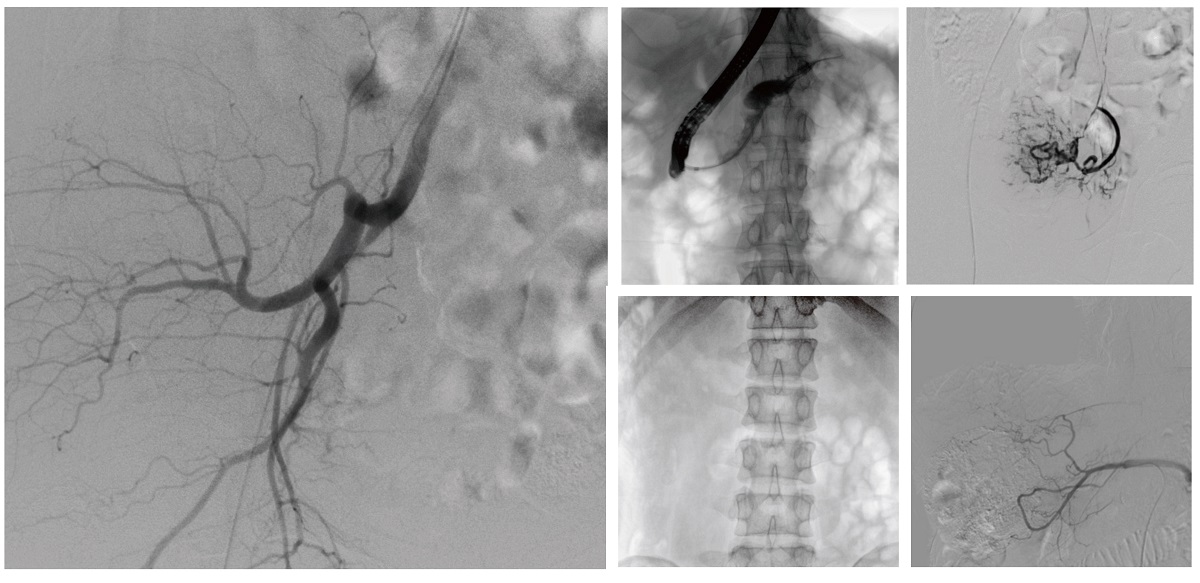

醫(yī)院引進(jìn)的普愛醫(yī)療移動(dòng)式平板介入中C,其高清成像能力覆蓋骨科、介入科、泌尿外科、婦產(chǎn)科等多科室,能夠滿足介入微創(chuàng)手術(shù)的多樣化需求。

設(shè)備的移動(dòng)式設(shè)計(jì),無需對現(xiàn)有手術(shù)室進(jìn)行改造,適合高負(fù)荷手術(shù)量或應(yīng)急情況下的靈活部署。如在急診介入手術(shù)中,該設(shè)備能迅速響應(yīng)需求,為醫(yī)生提供實(shí)時(shí)影像支持,提升搶救效率。